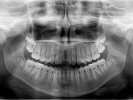

Ortopantomograma (OPG) / Panoramic X-Ray

Ortopantomogramareprezinta un examen rad ..